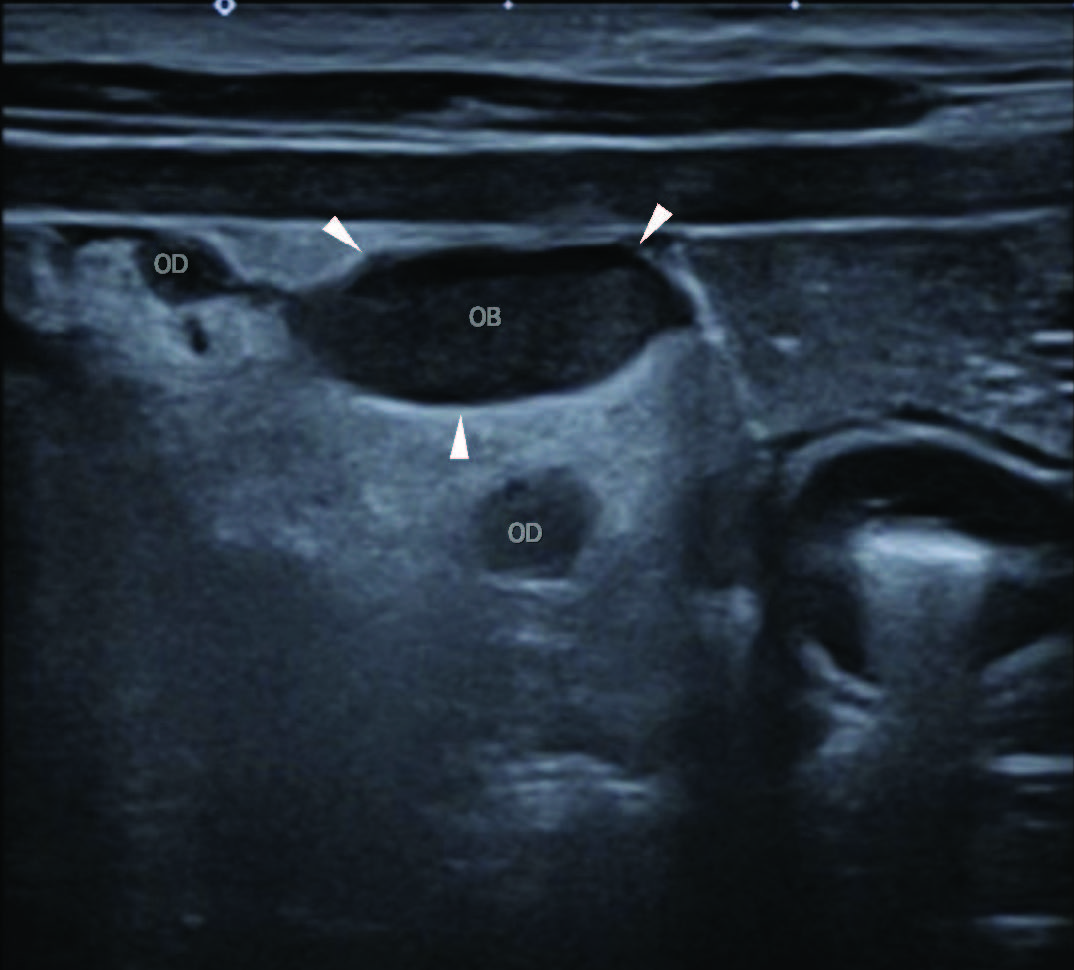

沿卵巢至子宫角卵巢端纵行,可见一略弯曲管状结构(最大径4 mm),无彩色多普勒信号,考虑为输卵管(图3、4)。此外,双卵巢均见多个圆形结构,符合黄体。病灶周围血供保留彩色多普勒信号。

图4. 使用高频线阵探头B模式,在左侧卧位进行的腹部超声横断面检查。图像左侧为外侧。注意右侧卵巢囊(OB;箭头示卵巢囊边界),以及部分纤细弯曲的管状结构,符合输卵管(OD;图像中位置最高者靠近卵巢囊,位置最低者邻近子宫角卵巢端)。